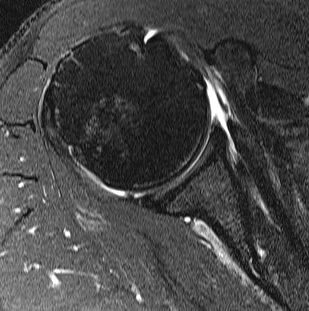

Goutallier classification

Amount of fatty degeneration in rotator cuff muscle belly on a T1 sagittal MRI

- systematic review of Goutallier grade and retear rates

- retear rates after surgical repair increase as the Goutallier stage increases

Stage 0: normal muscle

| Stage 1 | Stage 2 |

|---|---|

|

Some fatty streaks MRI shows some fatty streaks in supraspinatus |

More muscle than fat MRI shows grade 2 in supraspinatus |

|

|

| Stage 3 | Stage 4 |

|---|---|

|

Equal fat and muscle MRI demonstrates grade 3 supraspinatus and infraspinatus |

More fat than muscle MRI demonstrates grade 4 infraspinatus |

|